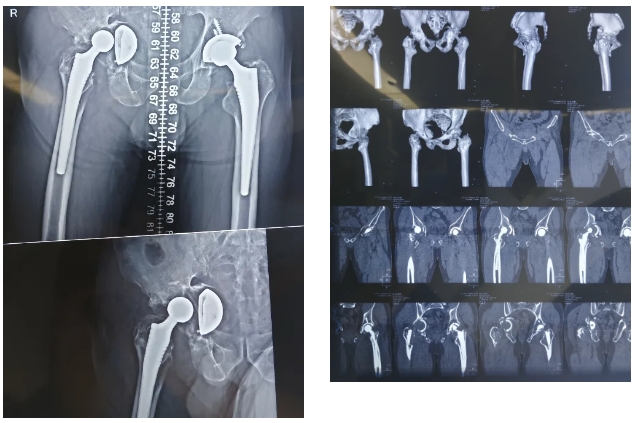

患者男,45岁,既往是一名保家卫国的的解放军战士,9年前因股骨头坏死行双侧全髋关节置换术,患者术后症状缓解。一月前,患者扭伤后自觉右侧髋部疼痛剧烈,就诊后摄X线示:髋关节脱位,髋臼骨折,耻骨骨折;因手术难度大,患者迟迟未接受手术治疗,患者辗转联系到我院骨科一病区张海军主任,完善髋部CT后发现患者术后右侧髋关节出现骨溶解,近一月来髋关节疼痛加剧并伴有活动受限。经影像学检查,发现患者髋关节假体脱位并翻转,骨盆不连续,伴有大量骨缺损,股骨侧近端骨溶解严重。此类患者手术难度极大,术中出血风险高,假体初始稳定性重建困难,术后并发症发生率较高。

(术前X-RAY)

(术后复查)